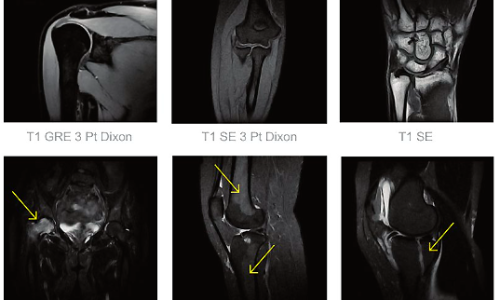

Risonanza Magnetica Aperta applicazioni principali

La Risonanza magnetica aperta RM è fondamentale per studiare in modo tridimensionale sia i tessuti molli che i duri e, grazie a procedure specifiche, facilita la diagnosi di varie patologie

Risonanza magnetica Ginocchio:** Indagini dettagliate per problemi di gonfiore, rigidità e dolore. Esplora ossa, cartilagine, menischi e tendini.

Risonanza magnetica Spalla:** Analizza lesioni tendinee, muscolari e fibrocartilaginee.

Risonanza magnetica Bacino:** Valuta la struttura osteo-articolare per diverse condizioni tra cui patologie traumatiche e oncologiche.